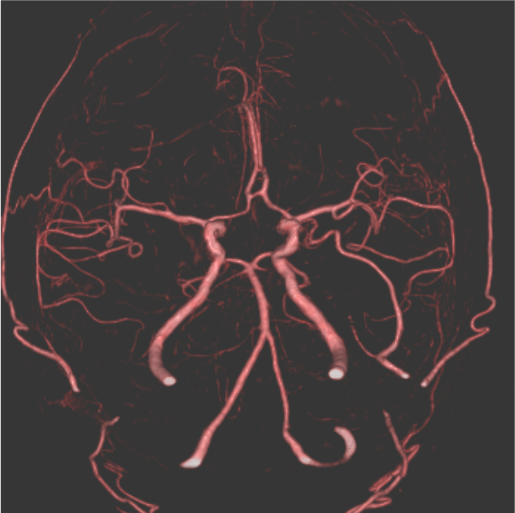

発症5日目に脳血管評価目的でCT angiographyの撮像依頼あり。MRI撮像ができないため、脳梗塞評価も兼ねて、全脳の多時相CT angiographyを撮像し、同一の収集データからCT perfusion画像も評価した。TIAの臨床診断であったが、単純CTとCT perfusionの所見から急性期~亜急性期ラクナ梗塞と診断した。

当該疾患の診断における造影CTの役割

急性期脳梗塞に対する血栓回収療法の適応判断においてCT perfusionの有用性が報告されている1-3)。CT perfusionは迅速にTmaxやCBFなどからischemic coreやpenumbraの評価が可能であり、また自動解析ソフトを用いることで客観的な定量評価が可能となる。320列CTで撮像すると、同じ撮影データから最適なCT angiographyやCT venography、多時相CT angiographyが再構成可能であり、脳梗塞の機序評価や血栓回収療法の治療戦略決定において有用である。本症例のようにMRI禁忌患者においては特にCT angiographyやCT perfusionが有用であった。

320列CTは寝台を移動することなく、1回のvolume撮影で16cmの範囲を撮像でき、時間分解能が高い全脳撮影が可能である。また、多時相のデータを収集するため、時間外にCTに不慣れな放射線技師が対応しても最適なCT angiographyを再構成することができる。なるべく右肘部から20Gでルート確保を行い、5mL/sで50mLの造影剤注入と同じ速度で生理食塩水の注入を行うこととし、注入速度を下げる場合は、撮像開始時間を遅らせている。